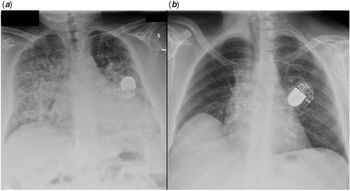

Chest X-ray disclosed bilateral confluent parenchymal infiltrates. (Fig 1a)

Figure 1. Chest X-ray, frontal view showing diffuse alveolar-interstitial infiltrates in case 2 (a) and normal lung fields in case 3 (b).

Nasopharyngeal swabs turned out to be positive for SARS-CoV2. High-dose steroids were started achieving progressive clinical improvement that allowed continuous positive airway pressure weaning after 1 week, and chest X-ray also progressively normalised.

Chest X-ray showed normal transparency of both lungs (Fig 1b). Table 1 reports lab results.